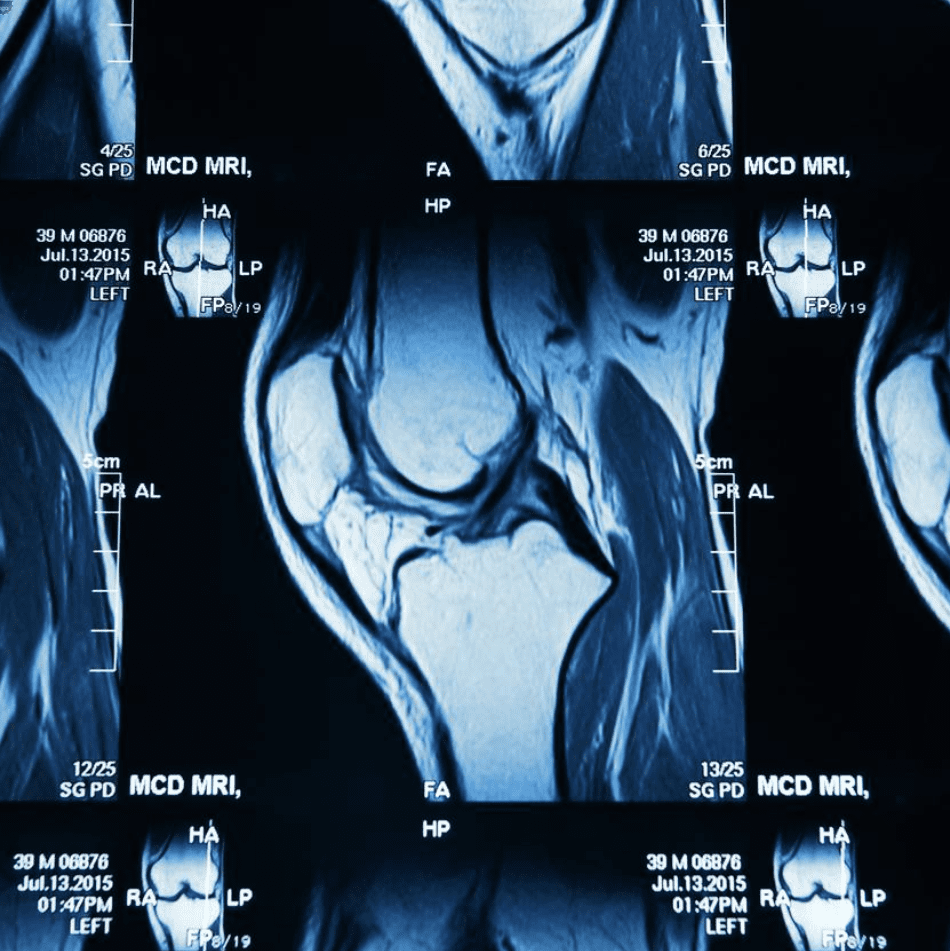

How To Fix A Tear Meniscus . There are some things you can do to ease symptoms of a meniscus tear. During this time, put ice inside a moist towel and put it on your injury for. Meniscus surgery is an operation that treats a torn meniscus. If the tear is too big to repair, your surgeon may remove all or part of the meniscus. The surgery requires a few small incisions and takes about an hour. The meniscus is a firm, elastic, shock absorber that helps stabilize the knee and is. You can ask a pharmacist about painkillers and the types of. Depending on the type of surgery and where it is located, success rates are as high as 80% up to 5 years after the operation. Surgery is a very effective way to repair a torn meniscus. Meniscus tear and repair surgeries tend to be effective. Both the inside and outside of the knee have a meniscus. Know what causes and how to treat meniscus tear, a knee injury that can be very painful and debilitating.

Answers to your questions about surgery to trim out a meniscus tear